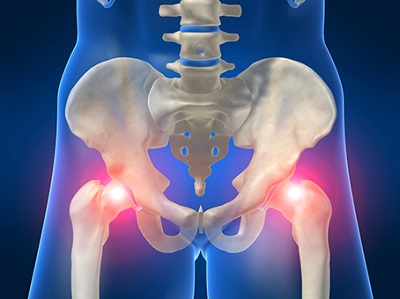

골반통증, 방치하면 큰 병 된다? 최근 들어 허리와 엉덩이 부위에서 느껴지는 ‘골반통증’ 때문에 고생하는 사람들이 늘고 있습니다. 특히 출산 후 여성이나 40대 이후 중년 여성에게 자주 나타나는 현상입니다.

이는 잘못된 자세로 장시간 앉아 있는 경우 근육 및 인대가 늘어나거나 손상돼 생길 수 있으면, 또한 평소 다리를 꼬고 앉거나 양반다리를 하고 앉는 습관도 골반통증의 원인이 될 수 있습니다.

하지만 대부분의 사람들은 이를 일시적인 근육통 정도로 생각하고 대수롭지 않게 여기곤 합니다. 그러나 문제는 골반통증을 그대로 방치할 경우 척추질환으로까지 이어질 수 있다는 점입니다.

따라서 초기에 적절한 치료를 받는 것이 무엇보다 중요하다는 점을 기억해야 합니다.

이번 포스팅에서는 골반 통증의 원인, 증상 등에 대하여 자세히 알아보겠습니다.